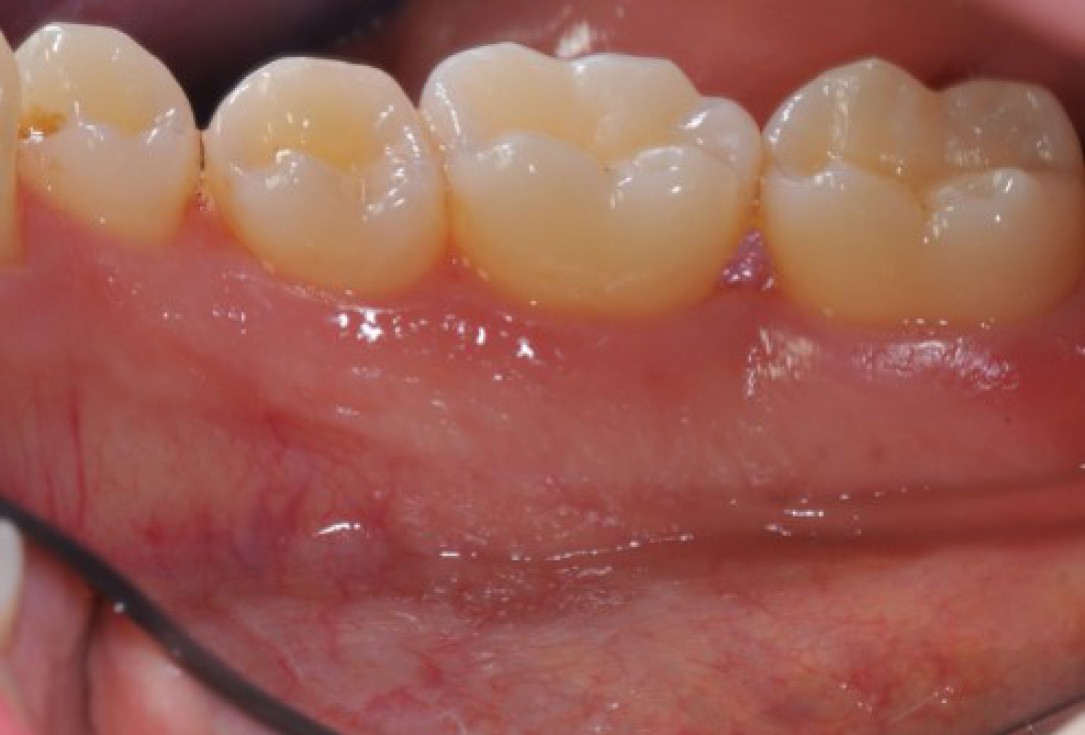

Initial situation: bone loss due to lack of physical load of bridge retained region 11